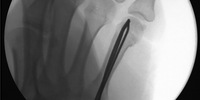

Dein Körper ist eine gut funktionierende Maschine. Wird ein Teil nicht gebraucht, fährt er dort die Energie auf ein Minimum zurück. Und zwar ruckzuck. Notstromversorgung sozusagen. Mein linker Arm kann ein Lied davon singen. Warum tut mir mein Körper das an? «Weil er clever ist», lautet die Antwort des Ergotherapeuten. Ich bin in Behandlung, nachdem ich mir beim Skifahren den linken Mittelhandknochen gebrochen habe, mit anschliessender Operation: